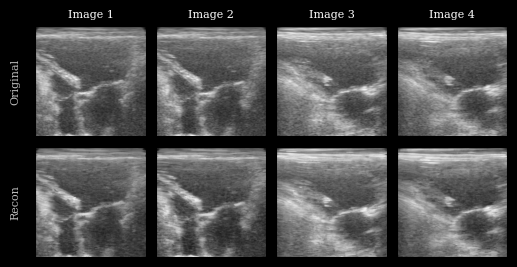

Visualization¶

We plot the original images and reconstructions for comparison.

fig.axes[0].set_ylabel("Original", fontsize=8)

fig.axes[n_imgs].set_ylabel("Recon", fontsize=8)